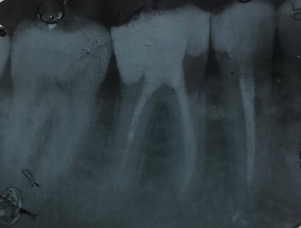

Un trattamento endodontico consiste nel salvare un dente compromesso da carie, traumi o fratture rimuovendone polpa e nervi infetti/infiammati responsabili di dolore, ascessi, cisti e granulomi.

Conservare denti naturali più a lungo possibile è infatti molto importante poiché attorno alle radici esistono dei legamenti che ci permettono di percepire e modulare la forza quando mastichiamo qualcosa.